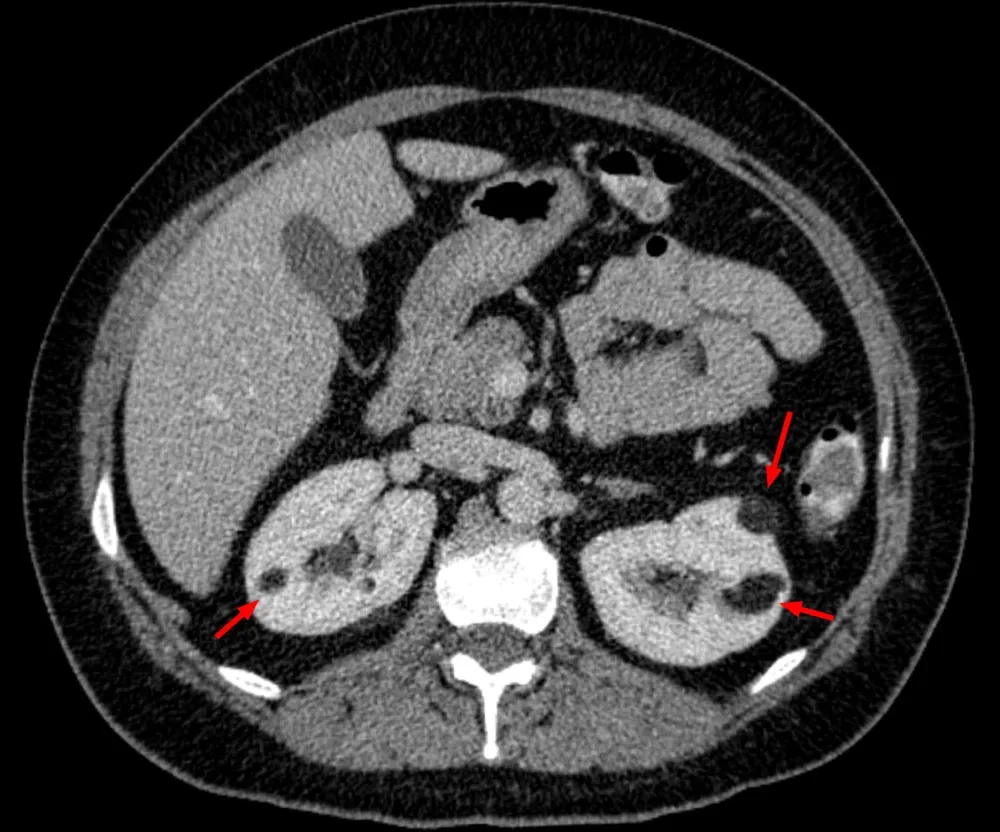

* Pacientes com **AML múltiplos (≥3), bilaterais e/ou grandes (ou seja, ≥4 cm)** têm maior probabilidade de ter CET (imagem abaixo). Nesses pacientes, é essencial realizar uma avaliação completa para CET, que inclui avaliação clínica, critérios diagnósticos e até testes genéticos.

TC abdome sem contraste evidenciando imagens hipodensas na região cortical de ambos os rins